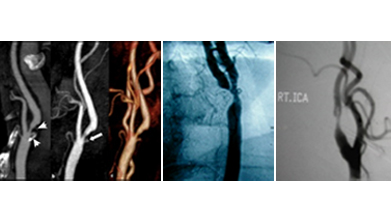

This is further investigated by performing a Carotid Doppler Sonography where all 4 vessels are examined, extent and degree of narrowing identified along with nature of the plaque, presence of thrombus.

Prior to intervention it is customary to get either an CT angiography or a Digital Subtraction Angiogram (DSA) done to look at the location and extent of the disease segment as well as the collateral circulation in the brain.

Choice of intervention includes either open surgery called “Carotid Endarterectomy” where the artery is cleaned of the diseased portion and then closed directly or with a patch (vein or synthetic – Dacron or PTFE) to increase the size of the artery or Endovascular procedure called “Carotid Angioplasty and Stenting”.

The choice of procedure depends on the location and extent of the disease segment, presence of clots and cardiac risk.